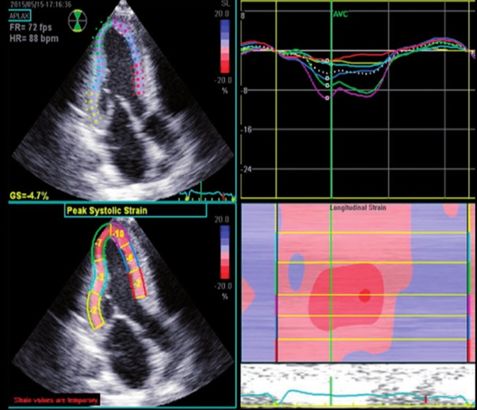

(C)斑点追踪技术是一种无创、可靠、定量的心肌运动评估方法,可发现各种病理状况下早期的心功能障碍。